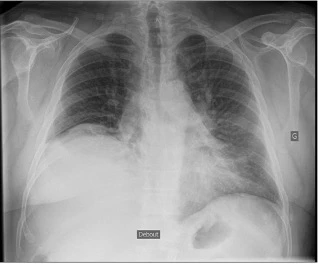

Un patient de 72 ans consulte pour une dyspnée aiguë de stade NYHA II apparue quelques jours après une chirurgie thoracique. Le patient est sous anticoagulation prophylactique. Dans ses antécédents, il a eu un AVP à l’âge de 20 ans, pour lequel il a été longtemps hospitalisé. Il n’a pas de traitement habituel.

Que montre sa radiographie thoracique ?